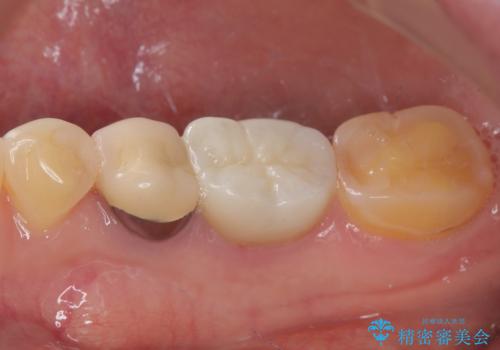

検診で見つかった齲蝕のセラミックインレー修復

- 検診で初期の齲蝕が見つかった患者様です。

これ以上神経の治療や被せものになりたくないため、初期のうちにしっかりとした治療をしたいとのことでした。

齲蝕をしっかりと除去して、精度の高いシリコーンによる型どりを行いセラミックインレーで修復しました。

唾液による接着阻害を防ぐために、ラバーダム防湿を行っています。